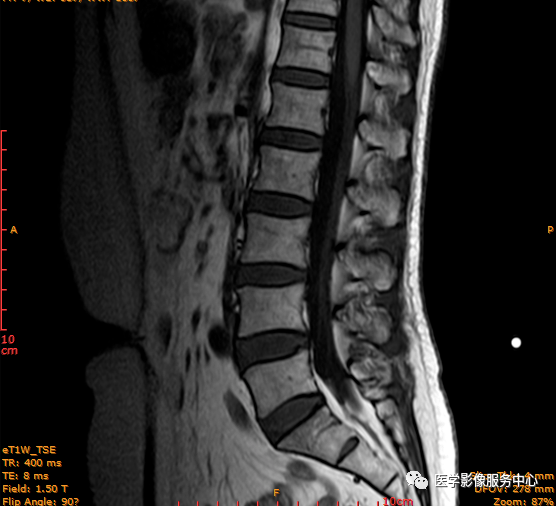

T1矢状位

这个患者腰椎间盘膨出程度不明显,神经根没有明显的受压,椎管未见明显狭窄,那这个患者腰疼的“罪魁祸首”是腰椎间盘膨出嘛?

日常工作因腰腿疼痛来检查腰椎MRI的很多,而腰腿疼痛并不一定就是腰椎椎间盘突出或膨出导致的,我们应该需要知道椎间盘HIZ也会引起腰腿疼痛,这种椎间盘源性的疼痛我们不能“忽略”;椎间盘后方HIZ并不少见,椎间盘后方 HIZ 在 T2WI 的局限性高信号、T1WI 呈局限性较低或等信号意味着通常所指的纤维环破裂伴随肉芽组织长入;而 T1WI、T2WI 均呈高信号可能是钙化组织。